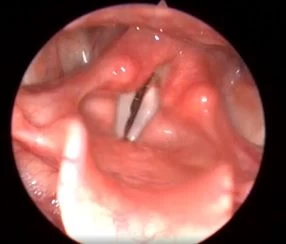

Клинический случай №4. Коагуляция новообразования правой части гортани с использованием лазера с длиной волны 445 нм.

Благодаря отличным свойствам по остановке кровотечения удалось уменьшить размер новообразования, что привело к облегчению всех симптомов, беспокоивших пациента до операции (кровохарканье, затруднение при глотании, ощущение инородного тела, охриплость голоса). Операция проводилась без отмены антикоагулянтной терапии, назначенной пациенту из-за сопутствующего заболевания.

Рис 4А. Новообразование (гемангиома) гортани справа. До хирургического вмешательства.

Рис 4Б. Новообразование (гемангиома) гортани справа. Спустя 13 месяцев после операции.